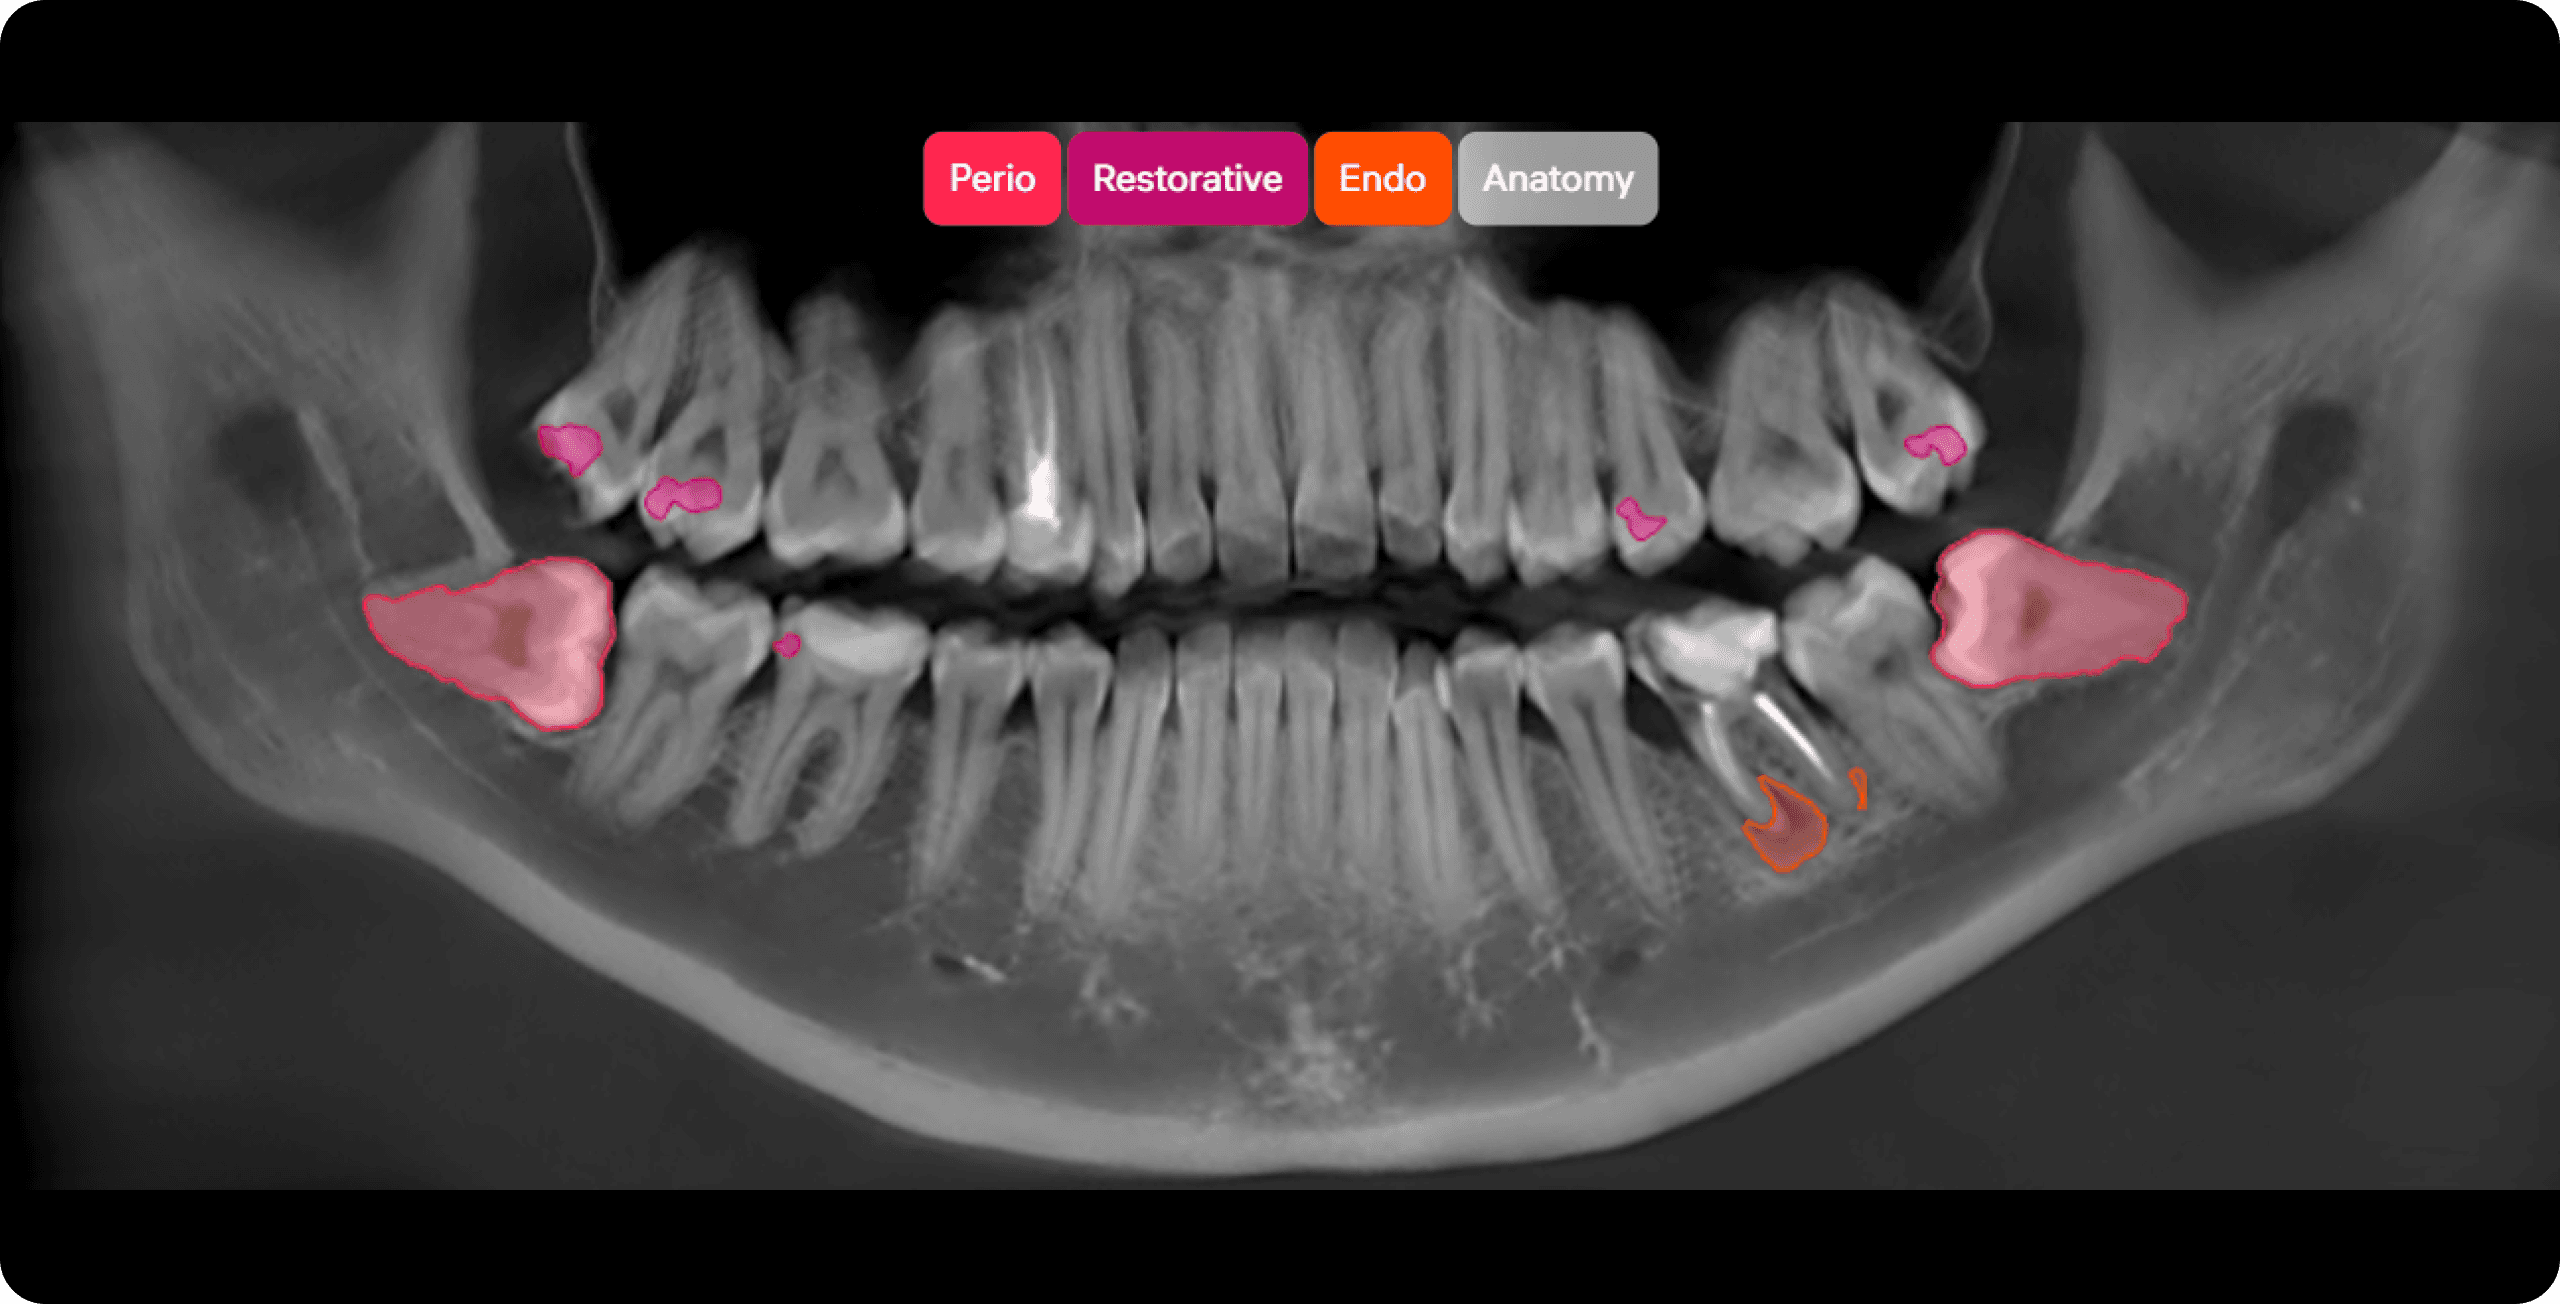

Diagnocat’s AI analysis of intraoral X-rays, panoramic X-rays (OPGs), and CBCT images produces an accurate, over 40 on 2D and over 60 conditions on 3D images.

Diagnocat detects over 60 tooth conditions in 3D images and 40+ in 2D

Endo-treated tooth

96 %

Impaction

100 %

Periodontal bone loss

87 %

Horizontall

Mild

Missed canal

74 %

Filling